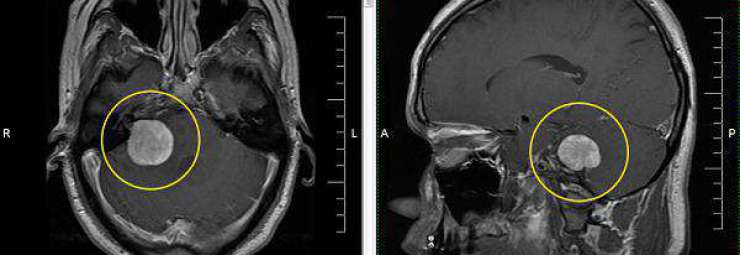

اورام الدماغ عند الاطفال

سرطان الدماغ عند الاطفال ورم الدماغ لدى الطفل أورام الجهاز العصبي المركزي ورم في دماغ طفل الورم الدماغي الخبيث للأطفال سرطان المخ و المخيخ BRAIN CANCER IN CHILDREN أسباب,أعراض,تشخيص,معالجة CHILD CENTRAL NERVOUS SYSTEM TUMORS تعتبر أورام الجملة العصبية أشيع الأورام الصلبة عند الأطفال , و تأتي في المرتبة الثانية بعد الابيضاضات (سرطان الدم ) في قائمة الأمراض الخبيثة من حيث نسبة الحدوث الإجمالية . و …